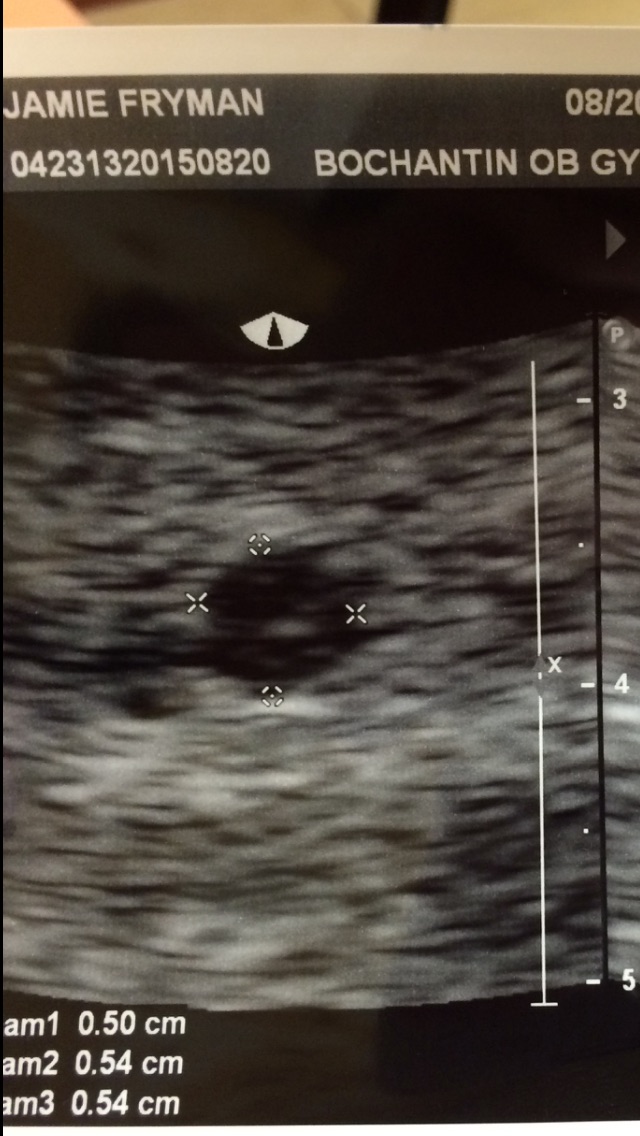

Here is our ultrasound pic! I was thinking I would be closer to 5 weeks but actually measured at 4 weeks. I go back in 2 weeks to see how things are going and hopefully hear a heartbeat!